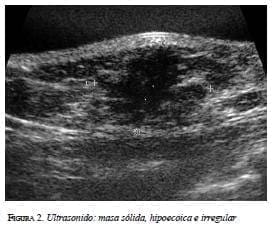

En la mamografía (figura 1a y 1b) se demostró una masa densa, irregular, de 3 x 2 cm en la región subareolar izquierda. Por ultrasonido (figura 2) se confirmó la pre-sencia de una masa sólida, hipoecoica e irregular. En la resonancia magnética (figura 3 a, b y c) se observó una masa hipercaptante, heterogénea, irregular, subareolar izquierda, de 3,5 x 2,5 cm, con curva de realce sospe-chosa tipo III. En todas las modalidades diagnósticas la lesión se clasificó según el sistema de datos y registro de imagen de mama (BI-RADS), como una lesión categoría V: altamente sospechosa de malignidad.